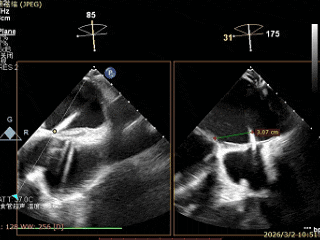

可降解房间隔缺损封堵器

选择靠下靠后穿刺位点,避开房间隔缺损封堵器,避免器械损伤

房间隔成功穿刺,穿刺位点距二尖瓣瓣环平面高度3.1cm,可使用高度不足